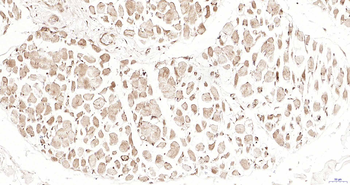

IHC analysis of PSMD4 using anti-PSMD4 antibody. PSMD4 was detected in a paraffin-embedded section of human lung adenocarcinoma tissue. Heat mediated antigen retrieval was performed in EDTA buffer (pH8.0, epitope retrieval solution). The tissue section was blocked with 10% goat serum. The tissue section was then incubated with 2 µg/ml rabbit anti-PSMD4 Antibody overnight at 4°C. Peroxidase Conjugated Goat Anti-rabbit IgG was used as secondary antibody and incubated for 30 minutes at 37°C. The tissue section was developed using HRP Conjugated Rabbit IgG Super Vision Assay Kit with DAB as the chromogen.